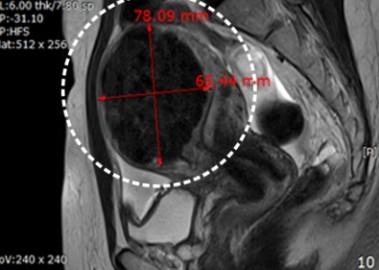

자궁근종 6cm 치료 전후

거대 자궁선근증 치료 사례